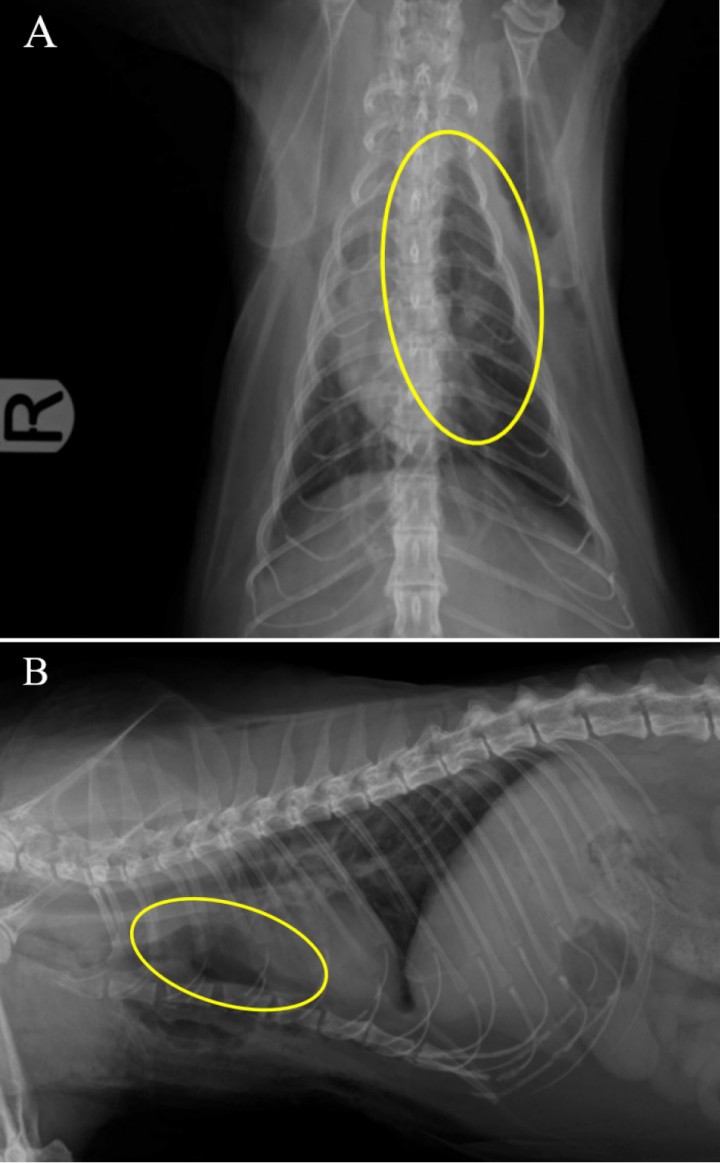

El resultado de la biopsia concluyó que se trataba de un timoma de tipo B1. El examen microscópico confirmó la presencia de una proliferación homogénea de linfocitos de pequeño tamaño con actividad mitótica y de áreas con células de mayor tamaño de tipo epitelial que se consideraron parte de un timoma. No se observaron células tumorales en los márgenes de la muestra, por lo que la resección fue completa (Fig. 5).

<p>Radiografías de tórax postquirúrgicas. (<strong>A</strong>) Proyección dorsoventral. (<strong>B</strong>) Proyección laterolateral derecha. Se observa la zona donde se localizaba el timoma con opacidad gas tras su extirpación quirúrgica (círculo amarillo).</p>

Radiografías de tórax postquirúrgicas. (A) Proyección dorsoventral. (B) Proyección laterolateral derecha. Se observa la zona donde se localizaba el timoma con opacidad gas tras su extirpación quirúrgica (círculo amarillo).